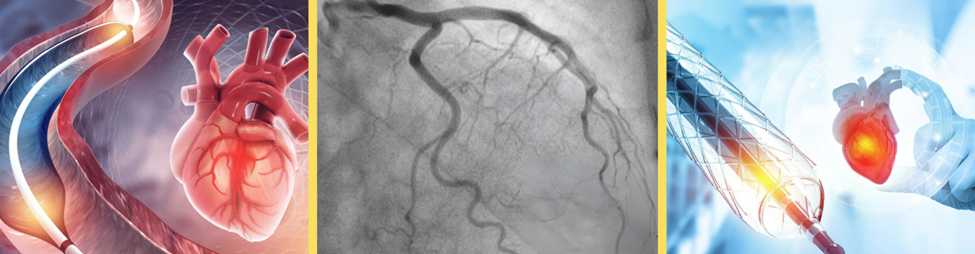

- Interventional diagnostic evaluations including right and left heart cardiac catheterization, coronary angiogram, and electrophysiology testing.

- Cardiac interventional management, including balloon angioplasty, rotational atherectomy, bare metal (BMS) or drug-coated (DES) stent placement (percutaneous coronary intervention or PCI) procedures.